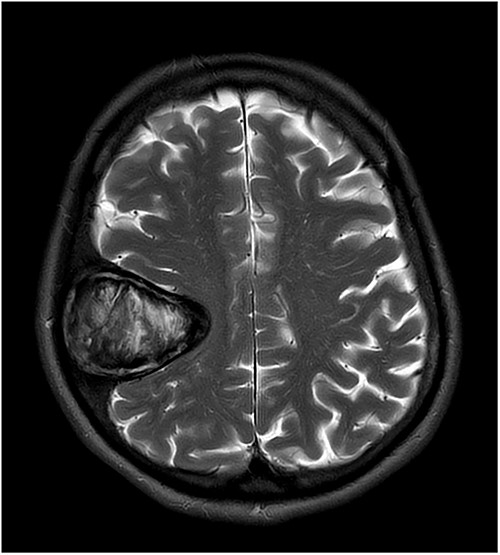

T2-weighted axial MRI scan showing the lesion with intralesional haemorrhagic products. There is no evidence of dural invasion.